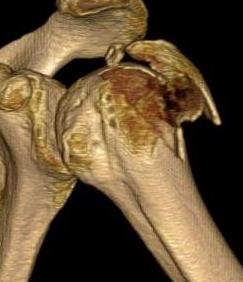

Four part

Avascular necrosis (AVN)

In most fractures, arcuate artery is disrupted, but head survives

- posterior circumflex artery is sufficient

- risk increases with amount of displacement

- 4 part fracture 30%

- 3 part fracture 15%